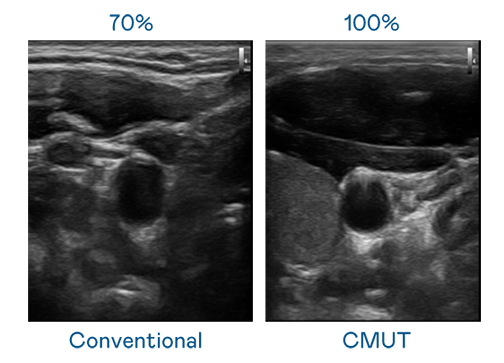

CMUT 技術是一種用電容式微機電元件來產生超音波訊號的技術。與傳統 PZT 壓電式技術相比,CMUT 頻寬增加 30%,更寬頻的超音波訊號讓影像解析度大幅提升,是實現高影像品質醫療超音波掃描、促進精準醫療發展的關鍵技術。

超音波影像的解析度高低,首先取決於探頭能發出的訊號頻寬。KY开元 CMUT 可提供高清晰的超音波訊號,提供高頻寬、高靈敏度、影像紋理細節更高的超音波影像,協助醫護人員縮短影像判讀時間及利用精準的醫療影像進行診斷。